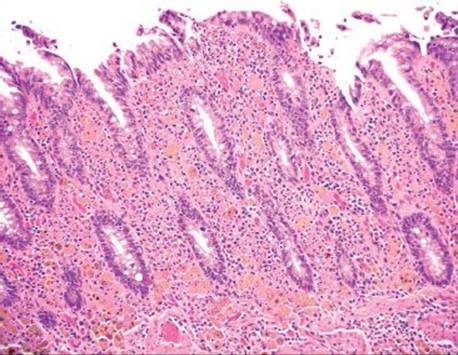

Melanosis coli refers to coarse, brown-black pigment in the cytoplasm of the colon’s resident macrophages. Despite the name, ultrastructural studies demonstrated the pigment is lipofuscin, not melanin (this particular factoid is a favorite among those who write test questions!).111 The pigment is derived from stimulant laxatives containing senna, aloe-emodin, chrysophanol, cascara, frangula, and rhein.112 The purgative effects of such preparations stem from their ability to increase colonic motility and decrease colonic absorption, resulting in decreased transit time and softer stools. The endoscopic images in patients with melanosis coli can be impressive (Fig. 4.231). Any region of the colon can be affected with no consistent regional pattern of involvement: some claim the distal colon is most affected, while others found the changes most pronounced proximally.113,114 Melanosis coli is seen in up to 73% of patients with chronic laxative usage and in up to 6% of biopsy and autopsy cases.115,116 Such findings have been documented within 4 months of regular laxative usage and the findings reverse 6 to 11 months following cessation (Figs. 4.232–4.238).117,118 Early literature suggested anthracoid laxatives were a risk factor for colonic neoplasia based on provocative animal and human studies showing an increased association of melanosis coli in patients with adenomas and carcinomas.119,120 Today, this theory has been abandoned.121,122

Figure 4.232 Melanosis coli. The characteristic brown-black pigment is within the cytoplasm of macrophages. The pigment is lipofuscin, not melanin.